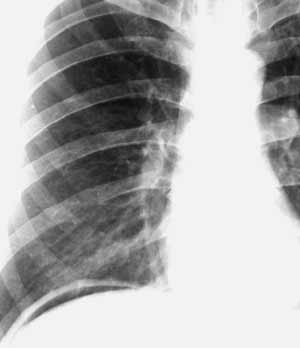

Рис. 5. Пневмоперитонеум - полоска просветления под правым куполом диафрагмы - следствие прободения язва двенадцатиперстной кишки.